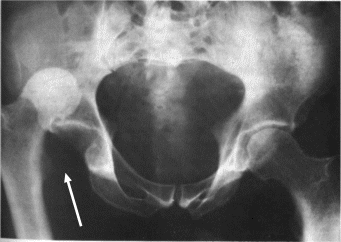

The injury itself – a posterior hip dislocation with a posterior wall fracture – means that the “ball” (femoral head) part of the “ball-in-socket” hip joint came out of the back (or posterior) part of the “cup” (or acetabulum.) On its way out, the “ball” (femoral head) knocked off a part of the back, or posterior, surface of the “cup” (posterior wall fracture.) This surface needs to be repaired surgically to re-create the full circumferential “cup” (acetabulum) and ensure future stability of the “ball-in-socket joint.”

It was 3rd and 4 and Tua was in the shot-gun formation. A weak-side blitz flushes Tua out of the pocket to extend the play, but he is tracked down by two defenders simultaneously. When he is tackled, he takes on the full weight of both defenders and lands primarily on his right knee while his hip and knee are both flexed – or bent – close to a 90-degree angle. This position with knee and hip both flexed to 90 degrees is similar to the position your leg is in when you are sitting in a chair – or in the front seat of a car. The injury Tua suffered – a posterior hip dislocation with a posterior wall acetabulum fracture – is a common injury in motor vehicle accidents and, as I mentioned earlier, often dealt with in the Orthopaedic Trauma world. However, with two SEC defenders plus his own body weight landing directly on his knee in the same position, the energy sent through Tua’s hip was quite similar to that of a motor vehicle accident.